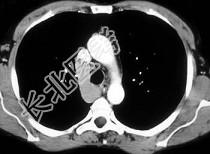

- 单项选择题主动脉后的团块是 ( )

A、腺瘤

B、神经纤维瘤

C、主动脉瘤

D、扩大的奇静脉

E、以上都不是